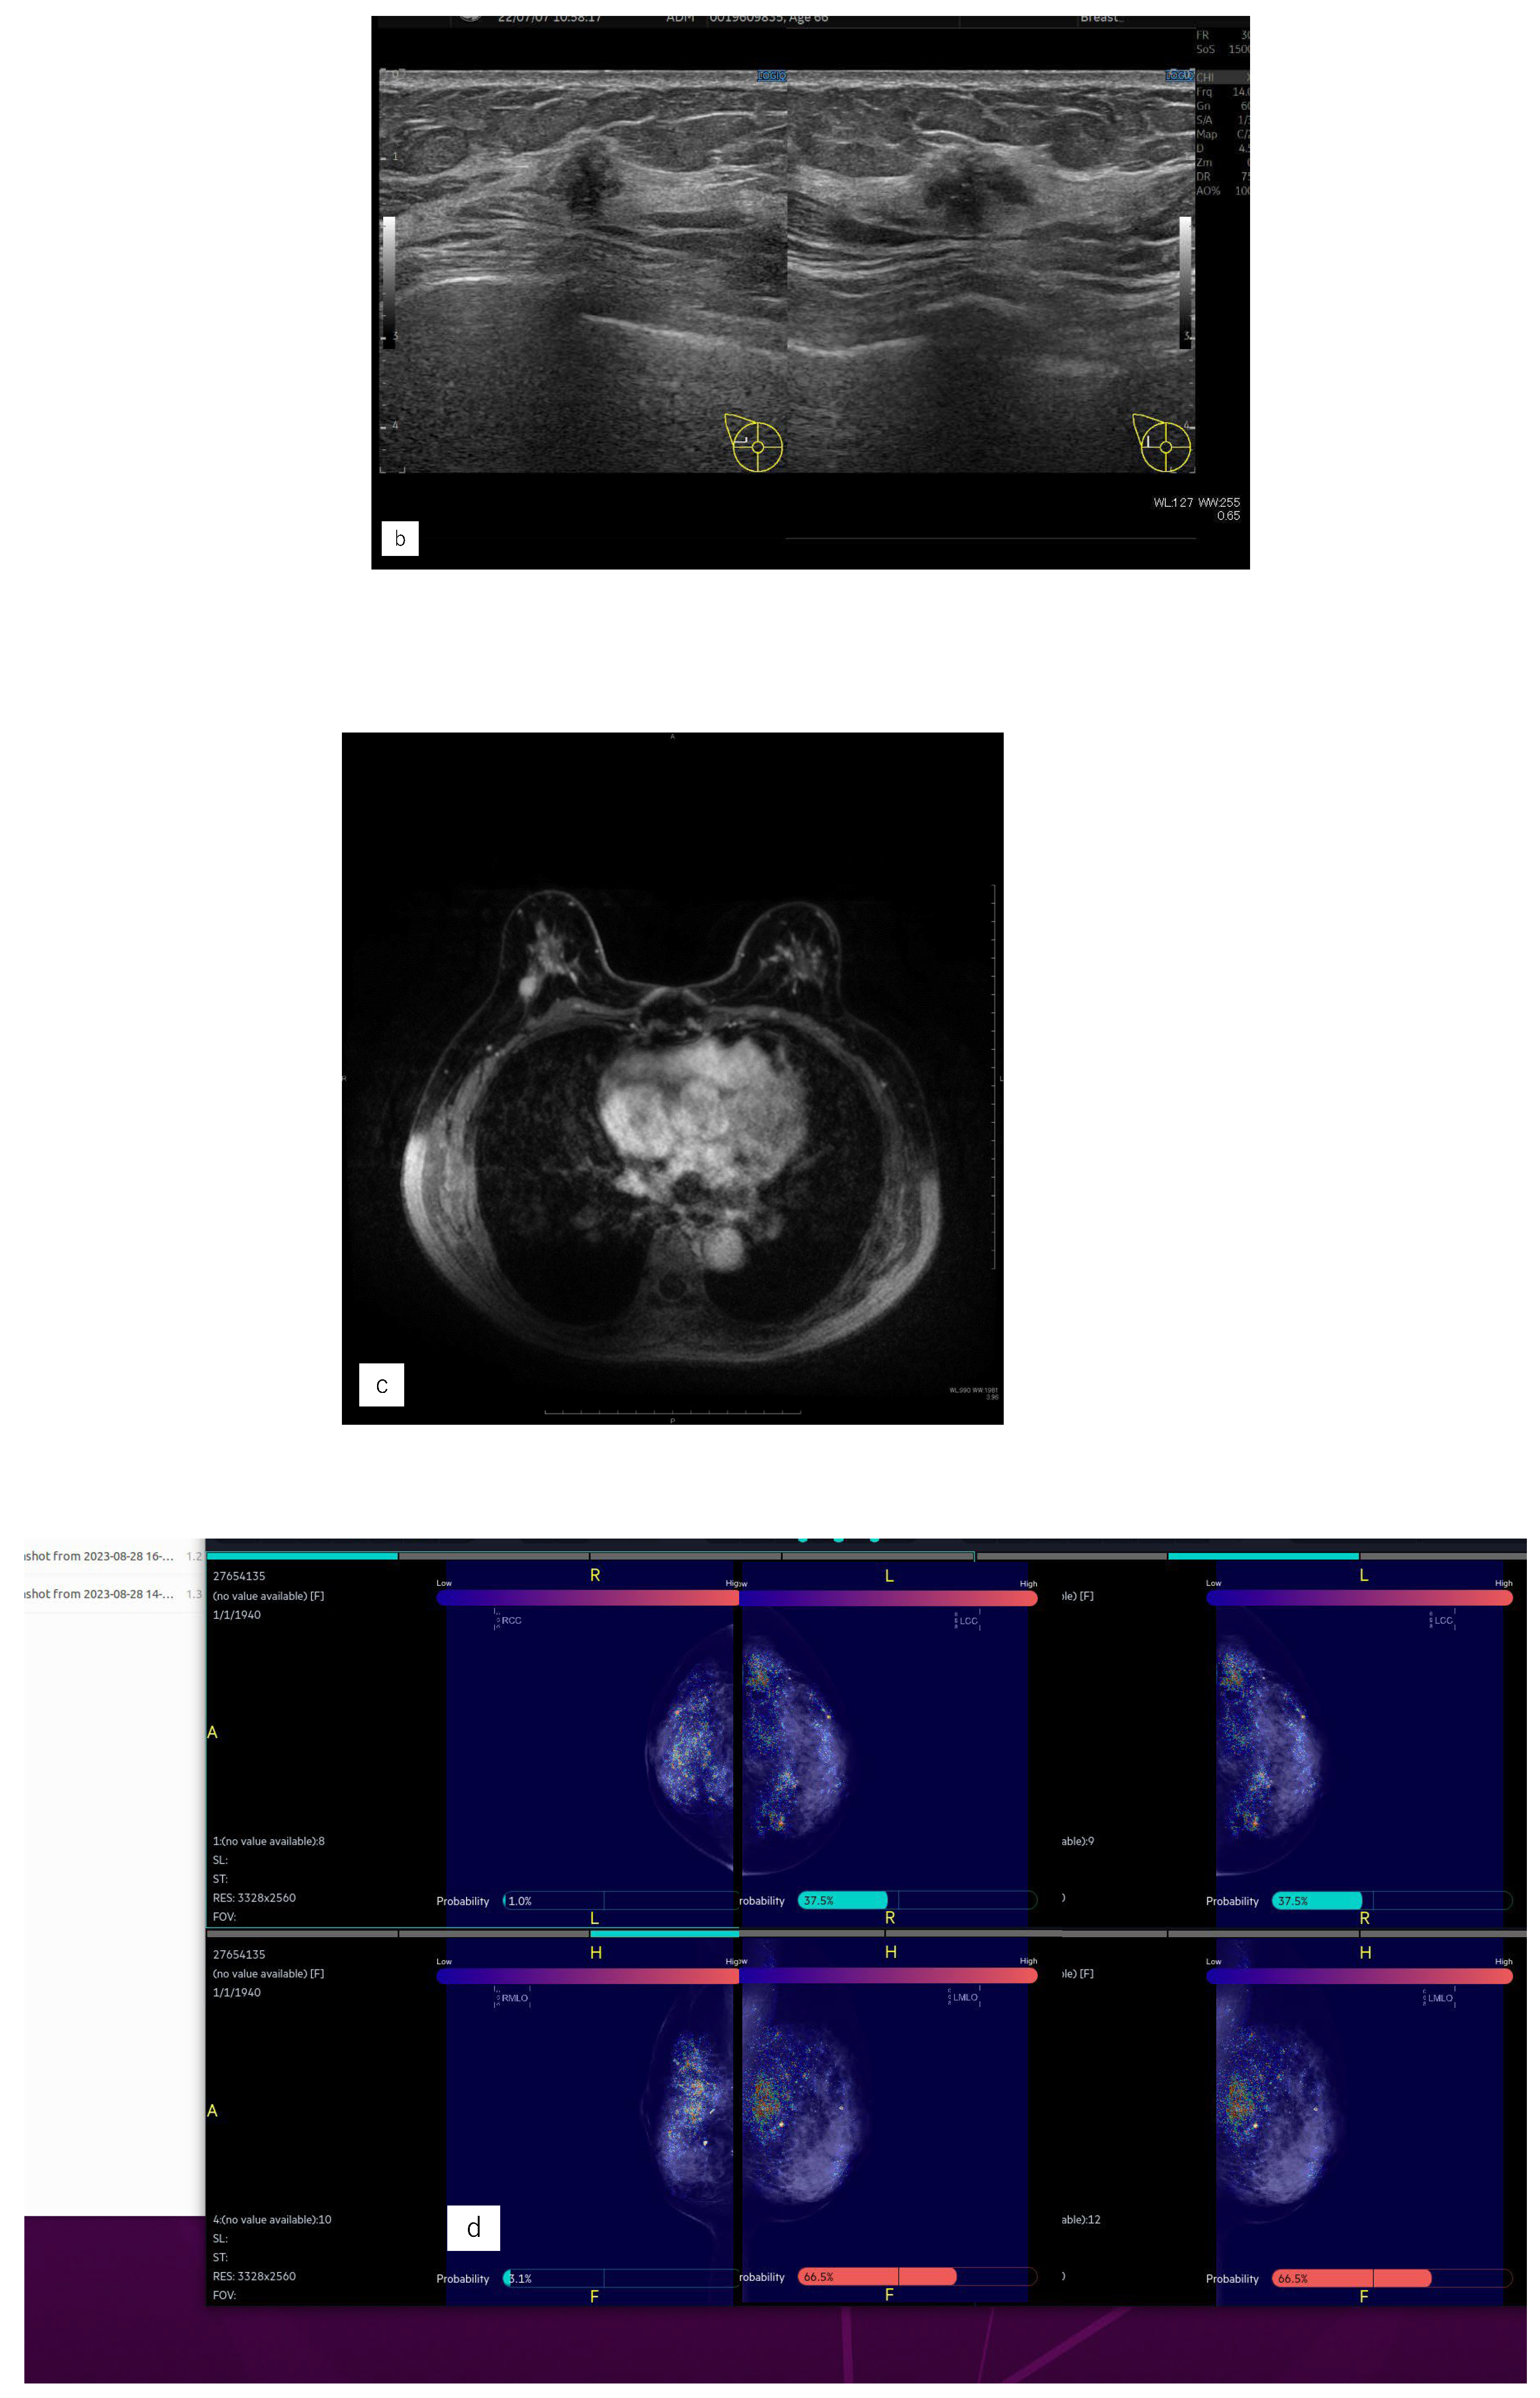

Figure 4. Representative case (case1). (a) MG. (b) US. (c) MRI. (d) AI diagnosis. (e) previous AI diagnosis.A 55 years old woman had left side breast cancer. Eight years later, she was diagnosed with right breast cancer. It was Lumina human epidermal growth factor receptor2 with 15 mm of invasive cancer and 15 mm of non-invasive cancer.(a) There were no malignant findings in the right side of mammography (MG).(b) Ultrasonography revealed a hypoechoic mass in the right outer area.(c) Magnetic Resonance Imaging revealed a mass with contrast enhancement of a total size of 37 mm in the right outer area.(d) The Artificial Intelligence (AI) system diagnosed malignant findings in the right breast based on MG at the time of diagnosis.(e) The AI system also showed areas of interest in MG prior to diagnosis and diagnosed as possibly malignant.